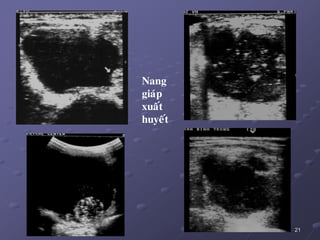

2/. Nhaân giaùp daïng nang:

a. Ñaëc tính:

 Nang giaùp thaät söï ít thaáy.

 Phaàn lôùn nang giaùp thöôøng gaëp laø nang keo do keát tuï

dòch keo trong caùc tuùi nang, dòch vaøng, seät. Khi coù xuaát

huyeát = nang giaû maùu (pseudo – heùmatique).

b. Hình aûnh SA: ña daïng, tuøy theo giai ñoaïn (tuoåi cuûa nhaân).

Löu yù: K gíap khoâng bao giôø bieåu hieän döôùi daïng nang hoøan toaøn.

21

Nang

giaùp

xuaát

huyeát